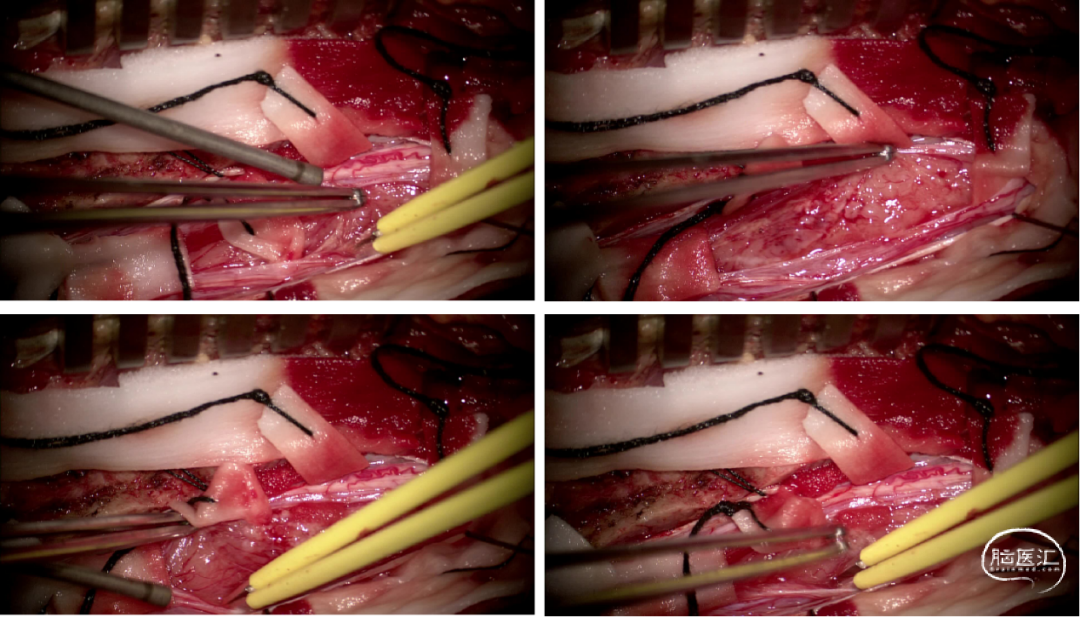

手术情况

硬脊膜张力高,脊髓向背侧膨出,与脊髓腹侧粘连紧密,肿瘤挤压脊髓,肿瘤边界分离,减少对胸髓的牵拉,降低了术后患者神经功能发生的概率,术后患者肢体麻木症状改善。